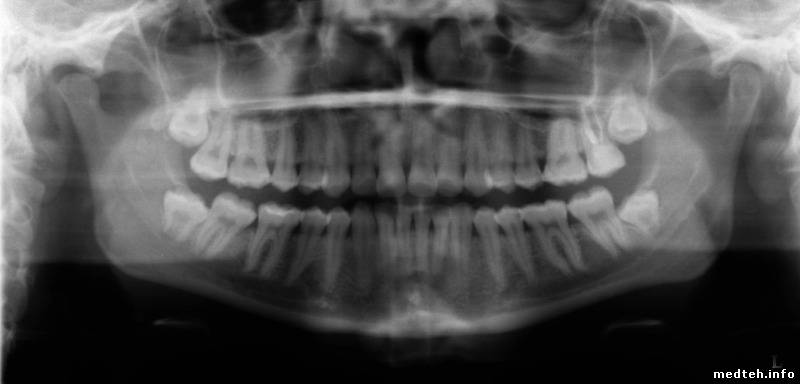

Аппарат новый. Снимок мутный, кость размыта .

Вот снимок

0856084.jpg (44.8 Kb)

разрешение не айс.

но: голова пациента отклонена назад(корни верхних резцов не в фокусе), шейный отдел позвоночника не вертикален. еще похоже, что режим не соответствует габаритам(добавить бы).

вроде нет смазывания на снимке, но не повредит.